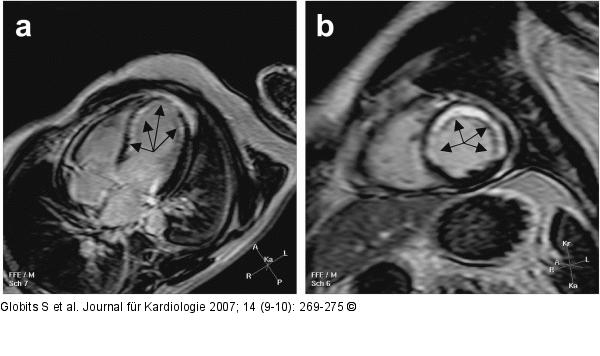

Abbildung 1a-b: Gradientenechosequenz Turbo-Gradientenechosequenz mit Inversionspuls 15 Minuten nach Kontrastmittelgabe in (a) axialer und (b) sagittaler Schichtführung bei Zustand nach Anteroseptalinfarkt: ausgedehnte Nekrose/Fibrosezone (Pfeile), die teilweise über 50 % der Myokarddicke betrifft und somit für überwiegend avitales Myokard spricht. |

Abbildung 1a-b: Gradientenechosequenz